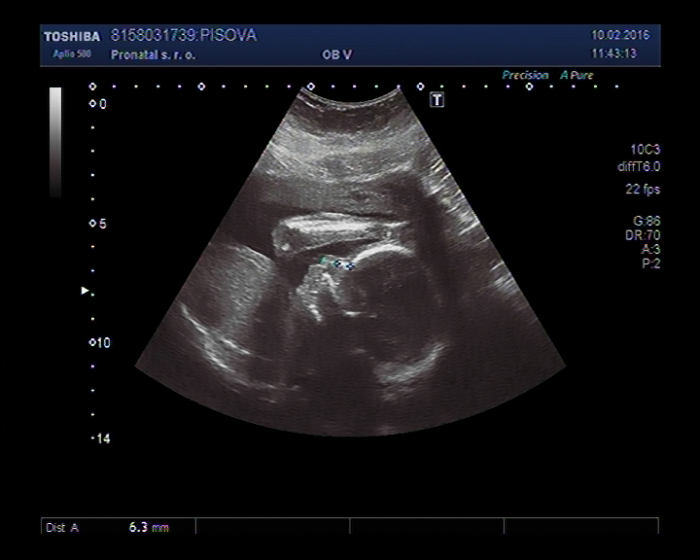

přidávám vám fotečku pro povbuzení te to z velkého UZ z 23tt